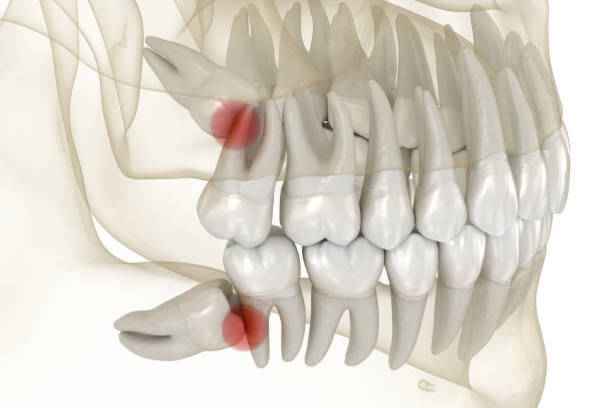

يختلف شكل ضرس العقل من شخص لآخر، إلا أنه غالبًا ما يتميز بحجم أكبر وجذور أكثر تعقيدًا مقارنة ببقية الأضراس. قد يكون مكتمل التكوين أو مشوهًا جزئيًا، وقد يظهر بشكل عمودي أو مائل أو حتى أفقي. هذه الاختلافات الشكلية تلعب دورًا مباشرًا في حدة اعراض ضرس العقل. ومن أبرز السمات الشكلية الشائعة:

• تموضع عميق داخل العظم دون ظهور مرئي.

مضاعفات ضرس العقل المدفون أو المتأثر

يُعد ضرس العقل المدفون من أكثر الحالات تعقيدًا في طب الأسنان، إذ يبقى محاصرًا داخل العظم أو اللثة. هذا الوضع يُنتج اعراض ضرس العقل بشكل أكثر حدة، وقد يسبب مضاعفات متعددة، منها:

• ضغط مستمر على الأعصاب المجاورة.

• تضرر جذور الأسنان المجاورة.